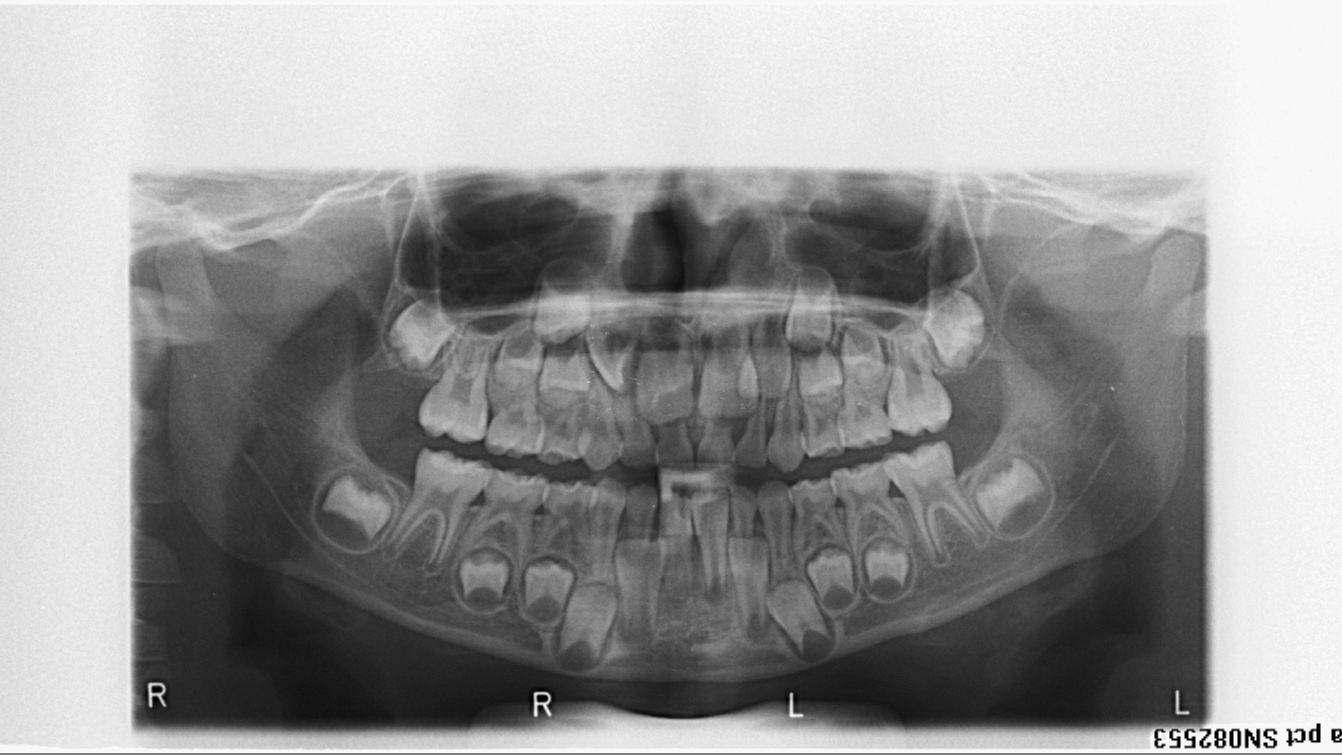

bilan des radiographies début et fin de traitement